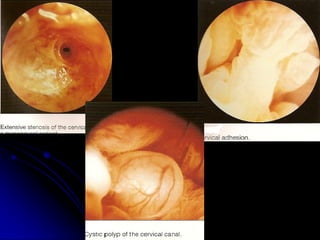

The document discusses the history and development of hysteroscopy. It began in 1869 but did not achieve routine use until improvements to optics, distension media, lighting and instruments in the 1970s-1990s allowed for office procedures without anesthesia. Today, many hysteroscopic procedures have replaced older, more invasive techniques. The document then provides details on rigid and flexible hysteroscopes, lighting sources, distension media, and diagnostic and operative uses of hysteroscopy for conditions like abnormal bleeding, infertility, uterine anomalies and assisted conception. Contraindications are also outlined.